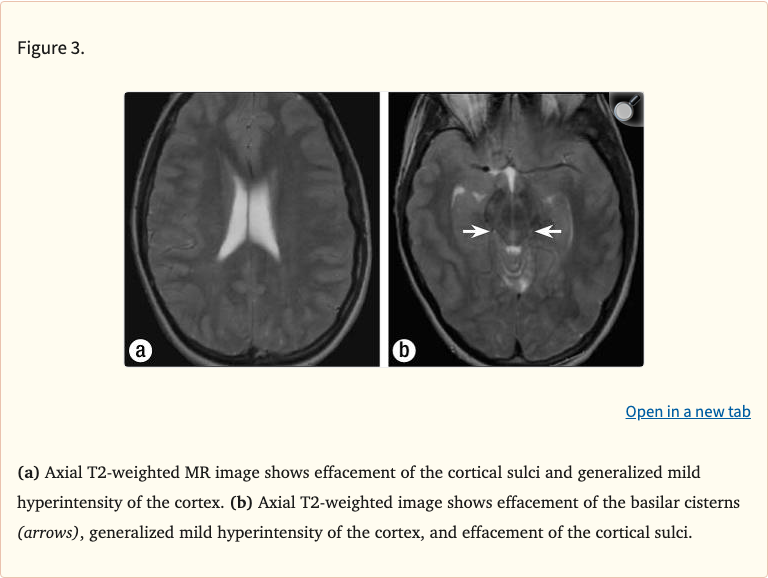

Figures